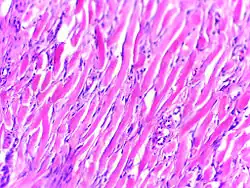

Histologically, keloids are fibrotic tumors characterized by a collection of atypical fibroblasts with excessive deposition of extracellular matrix components, especially collagen, fibronectin, elastin, and proteoglycans. Generally, they contain relatively acellular centers and thick, abundant collagen bundles that form nodules in the deep dermal portion of the lesion. Keloids present a therapeutic challenge that must be addressed, as these lesions can cause significant pain, pruritus (itching), and physical disfigurement. They may not improve in appearance over time and can limit mobility if located over a joint.[16]